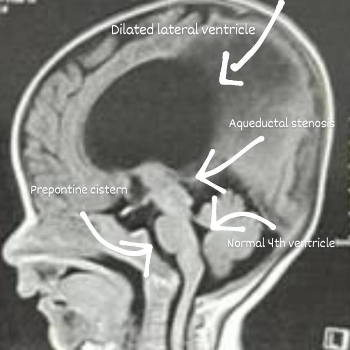

In the heart of Mumbai, nestled within the bustling streets, lies a story of hope, resilience, and medical brilliance. This is the story of Aarav, a spirited 6-year-old, and his battle with a life-threatening brain condition. For Aarav’s parents, Priya and Rajesh, their world turned upside down one fateful afternoon when Aarav suddenly collapsed while playing in the park. The diagnosis was grim – a complex brain tumor that required immediate medical intervention.

Aarav’s case was challenging. The tumor was located in a sensitive area of the brain, and the risks were high. However, Dr. Rege’s calm demeanor and thorough explanation of the procedure reassured Priya and Rajesh. He detailed the minimally invasive techniques he would use, designed to reduce recovery time and minimize complications.